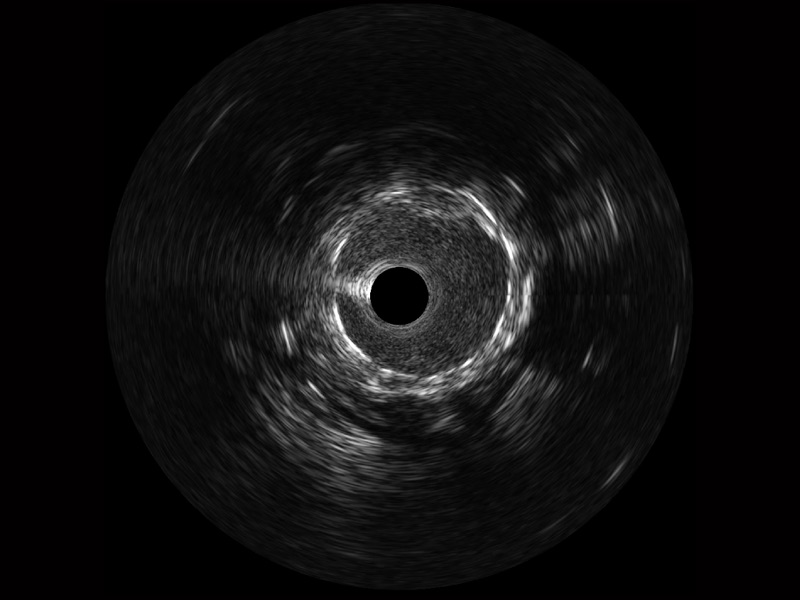

球速体育入口宽频IVUS图像

对比传统IVUS导管成像,球速体育入口宽频IVUS图像的近场支架梁显影更细腻,远场中膜外血管仍清晰可辨,兼顾远中近,兼顾分辨力与穿透深度